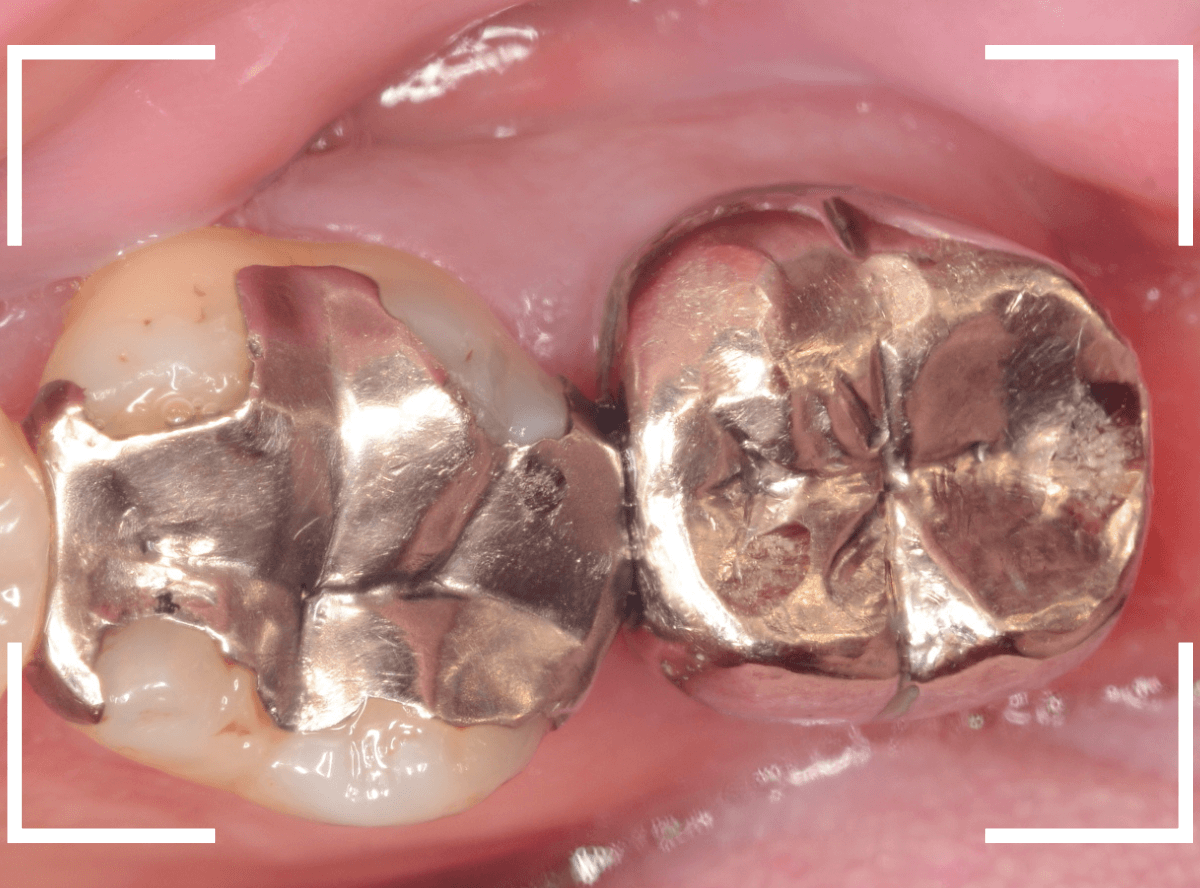

Case.20 メタル・インレーとメタル・クラウンをジルコニアにやり替え

「下の奥歯の銀歯を白くしたい」というご希望の患者さんです。

メタル・インレーとメタル・クラウンが入っていますね。

検査の結果、再製に問題なさそうでしたので、治療を進める事になりました。

治療前後の写真になります。

やはり、印象が大きく変わりますね。